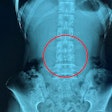

Although most lumbar spine MR images are normal, radiologists typically use sagittal T2, short-tau inversion recovery (STIR), and high-resolution T1 imaging of the lumbar spine with axial T2 sequences through the two most caudal disk spaces. The most common abnormalities are disk degeneration and small disk herniations that are often incidental subclinical findings. STIR and high-resolution T1 acquisitions can detect spondylolysis.